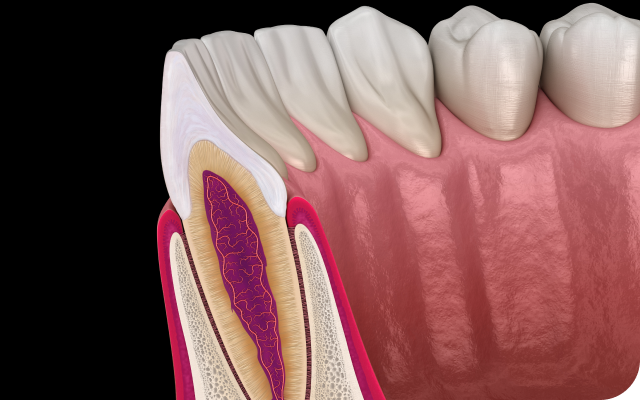

자연치아는 인공 보철물이 대체할 수 없는 기능과 가치를 지니며

치아와 잇몸의 조화를 이루어 구강의 생리적 안정성을 유지하는 핵심입니다.

신경치료는 단순히

치아 속만 치료하는 것이 아닙니다.

치아를 지탱하는 잇몸과 치조골의 건강까지 함께 고려하는 신경치료,

치주과 전문의가 치아와 주변 조직 상태를 종합적으로 평가한 후

치료를 진행합니다.

바른선택치과의원은 치아와 치주 조직을 함께 관리하여

재발 위험을 낮추고, 자연치아를 보존하는 치료를 지향합니다.